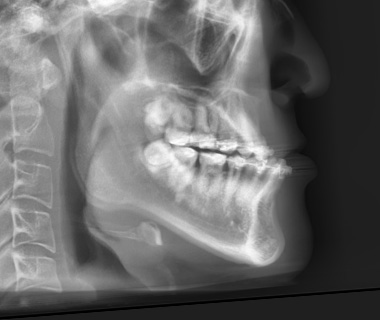

아래턱이 위턱보다 앞으로 나와 보이거나 옆모습에서 턱이 길고 강하게 돌출된 상태를 주걱턱이라 합니다.

이러한 모습은 부정교합을 동반하는 상하악의 길이, 위치 관계 이상(골격성 3급 부정교합) 혹은 턱끝의 과도한 발달로 인해 나타납니다.

턱끝 부위만 돌출된 주걱턱

- 악골 구조는 비교적 정상

- 턱끝의 길이돌출로 하관이 커 보이는 경우

- 기능 문제는 크지 않은 경우가 많음